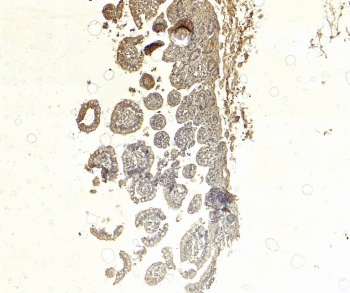

IHC staining of FFPE human small intestine tissue with SGLT1 antibody at 5ug/ml. Required HIER: steamed antigen retrieval with pH6 citrate buffer; HRP-staining.

Negative control: IHC staining of FFPE human small intestine tissue without primary antibody. Required HIER: steamed antigen retrieval with pH6 citrate buffer; HRP-staining.